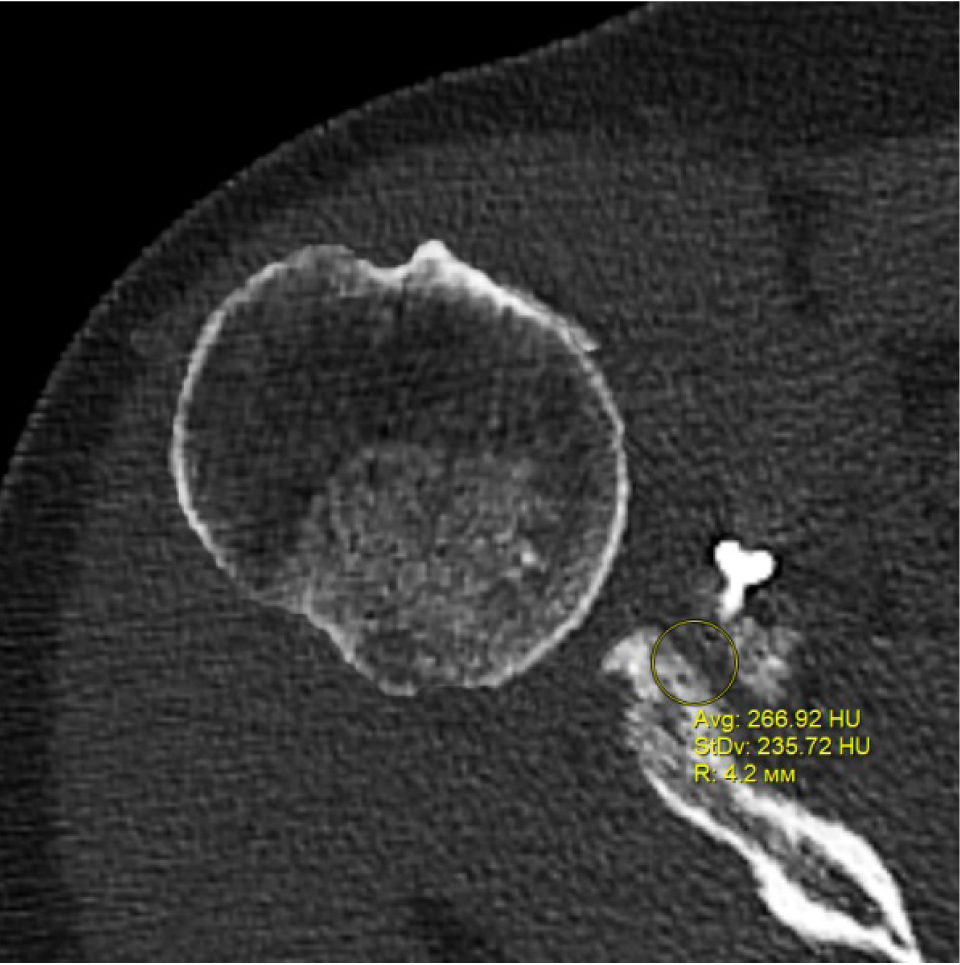

В программном обеспечении, на аксиальных КТ срезах оперированного плечевого сустава, выбирали инструмент «круг», который позволял посчитать среднюю плотность тканей внутри круга в единицах Хаунсфильда. Шкала единиц Хаунс-филда (HU) – шкалалинейного ослабления излучения по отношению к дистиллированной воде, рентгеновская плотность которой была принята за 0 HU (при стандартных давлении и температуре). Круг устанавливали таким образом, чтобы одна его половина была заполнена тканью гленоида, вторая половина тканью трансплантата (рис. 1–3). Оценивали плотность тканей над проксимальным винтом, между винтами, под дистальным винтом. Полученные данные анализировали с помощью пакета Microsoft Excel.

Рис. 1. Оценка плотности ткани под дистальным винтом